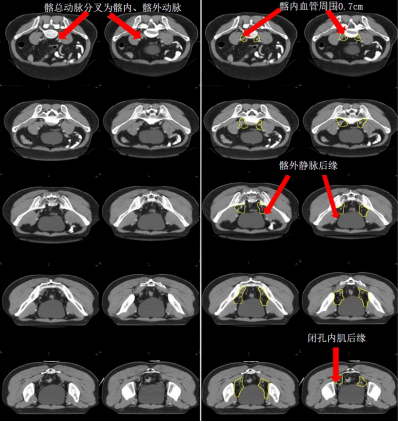

c) 髂內淋巴引流區-LLN P(黃色) (圖 8)邊界:

上界:髂總動脈分叉為髂內、外動脈處;

下界:肛提肌插入外括約肌處/骨盆底;

前界上:血管外 0.7 cm;

前界中:輸尿管進入膀胱的虛擬冠狀平面,髂外血管上段的后方;

前界下:閉孔內肌后緣;

后界:骶髂關節外側緣;

內界上:血管周圍 0.7 cm(直腸系膜以上),不必避開正常解剖結構;

內界中/下:直腸系膜筋膜,盆腔器官;

外界上:髂腰肌,骨盆;

外界中/下:盆壁肌肉(梨狀肌和閉孔內肌)的內側緣。

圖 8 直腸癌髂內淋巴引流區 CTV 勾畫示例

d) 閉孔淋巴引流區-LLN A(紫色) (圖 9)邊界:

上界:股骨頭頂;

下界:閉孔動脈離開骨盆層面;

前界中:髂外血管后壁;

前界下:當髂外血管離開骨盆或閉孔動脈前緣;

后界:閉孔內肌后緣或髂內淋巴結區前緣;

內界:直腸系膜筋膜,盆腔器官;

外界:閉孔內肌的內側緣。

圖 9 直腸癌閉孔淋巴引流區 CTV 勾畫示例

e) 髂外淋巴引流區-EI(灰白色) (圖 10)邊界:

下界:旋髂深動脈與髂外動脈交叉處或者髖臼頂部與恥骨上支連接之處;

前界:血管前方 0.7 cm,髂腰肌前外側 1.5 cm;

后界:髂外靜脈后緣;

內界:血管內側 0.7 cm,避開盆腔器官;

外界:髂腰肌。

圖 10 直腸癌髂外淋巴引流區 CTV 勾畫示例